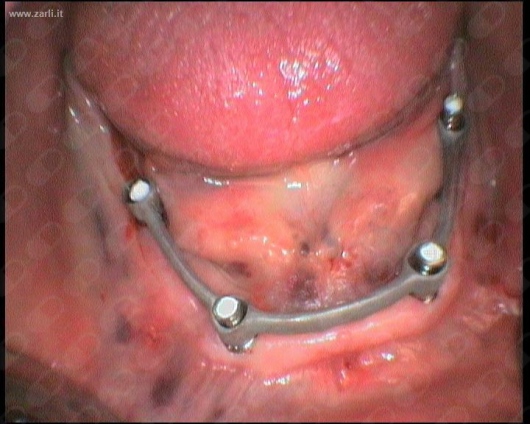

Chirurgia implantologia, Protesi su impianti con chirurgia guidata

• Implantologia